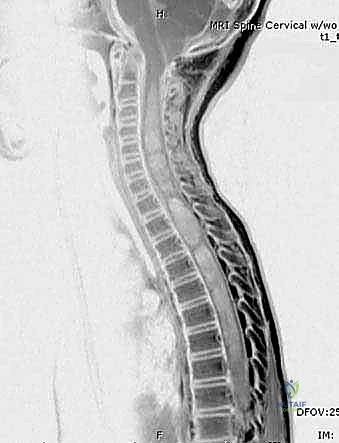

* السنسنة المشقوقة (Spina Bifida): تشوهات في الحبل الشوكي تؤثر على الإمداد العصبي لعضلات القدم.

- الرنين المغناطيسي (MRI): يُستخدم في حالات محددة لتقييم الأنسجة الرخوة، الأربطة، أو لاستبعاد تشوهات الحبل الشوكي.